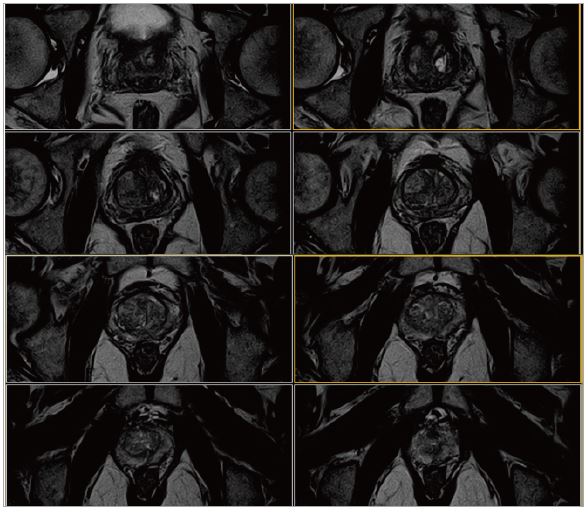

Рис. 10. Аксіальне, Т2-зважене зображення (за протоколом mpMR).

Рис. 11. Аксіальне DWI – A=b0, B=Iso b800, C=Iso b1000 e, D=Iso ADC (за протоколом mpMR).